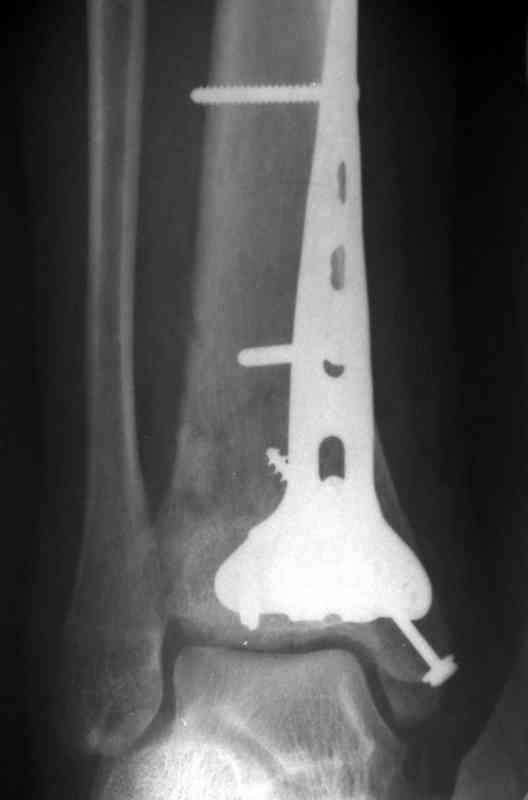

Это типичный перелом пилона, который надп лечить только открыто.Извини те что опоздал к обсуждению, но даже если вы уже оперировали больного по Илизарову это даже лучше.Посылаю картинки.

Посмотрим вроде прошло если понравится напишите расскажу как это сделать.По принципам АО кстати при поступлении сначала восстанавливают длину малоберцовой кости фиксируют пластиной 1/3 трубки потом накладывают аппарат наружной фиксации и через 7-10 дней открыто восстанавливают большеберцовую кость.С уважением Дрягин

На рентгенограммах типичный перелом пилона по типу С-3. есть опыт до 100 открытых опреаций у нас в клинике. 20 примерно в год. Принцип один -все внутрисуставные переломы нуждаются в открытой репозиции и внутренней стабильной фиксации. При поступлении КТ не надо, так как получается только нагромождение костей. Истинной картины нет. Главное восстановить длину малоберцовой кости - это ключ к успеху. При поступлении меньше всего надо думать о сосудистых расстройствах, т.к. сама операция и репозиция даже сначала частичная даёт улучшение сосудитых нарушений. Причём очень быстро. Операция в 2этапа. При поступлении доступ позади наружной лодыжки, причём обязательно. После этого репозиция малоберцовой кости и фиксация пластиной 1/3 трубки под винт 3,5. Дренаж и любой аппарат наружной фиксации. Затем после спадения отёка на 5-7-10 день аппрат снимается и дугообразный разрез спереди от медиальной лодыжки 10-12 см. Главной чтобы расстояние между 1 и вторым разрезом было не меньше 7-8 см. Тогда не будет некрозов лоскутов. Таранная кость используется как матрица на неё укладываются отломки и фиксируются пицами. Ренг-контроль. Отломки лежат все отдельно, но ничего не высыпется. При переломах С-3 всегда нужна костная пластика (из крыла). Фиксация пластиной лист клевера простой или LCP. Гипс не нужен. Дренаж до 48 часов. Операция длится 3-4 часа обязательно без жгута. Посылаю примерно такой же случай.

Послала ещё два снимка, если не пройдут, пошлю ещё. Дрягин. Если есть вопросы, готов ответить.

Посылаю результат лечения предыдущего больного через год.